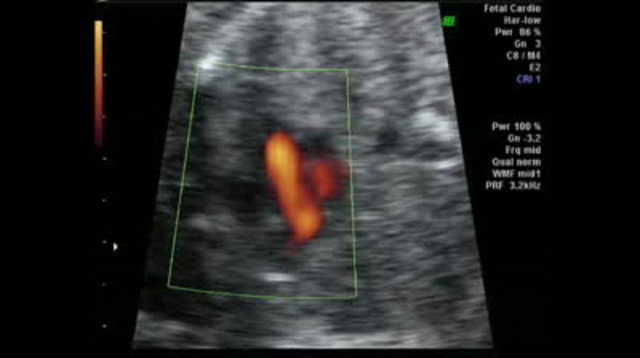

• Prenatal- Heartbeat

Prenatal- Heartbeat

Heartbeat is something our heart does several times in a minute and keeps us alive. Think, we have been doing that since we were only 5 weeks old as an embryo. This is a sign of the amazing development of the beginning of the circulatory system. This momentous heart beating occurs in the embryonic stage as it teaches us in our book is from 2 to 8 weeks. This pictures shows an ultrasound of a embryo's heartbeat. Image found on Google Images.